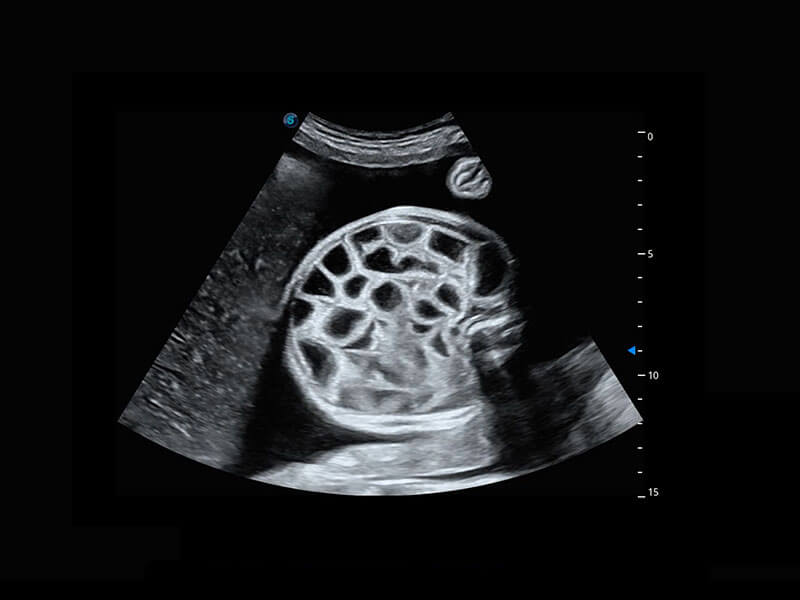

腔内三维-宫内节育器

腔内三维-光影成像

高分辨率容积成像-早孕胎儿

光影成像-孕囊